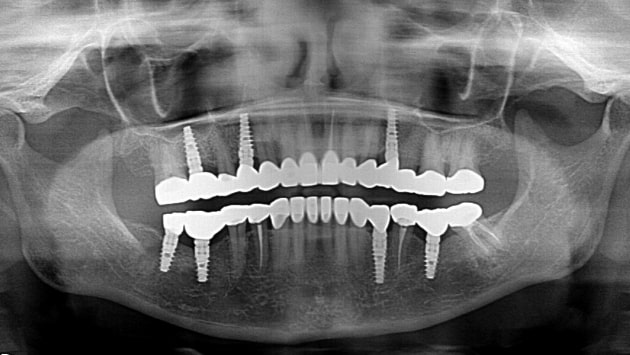

All on 4 is a patented treatment that requires only four

implants for a dental restoration. Through this procedure

you will obtain impeccable and highly stable teeth that

provide immediate improvements in eating comfort,

esthetics and speech.

A specialist will evaluate your dental status using X-rays, panoramic photos of your mouth, a 3D CBCT scan, and other techniques to provide you with the best treatment options and suggestions.